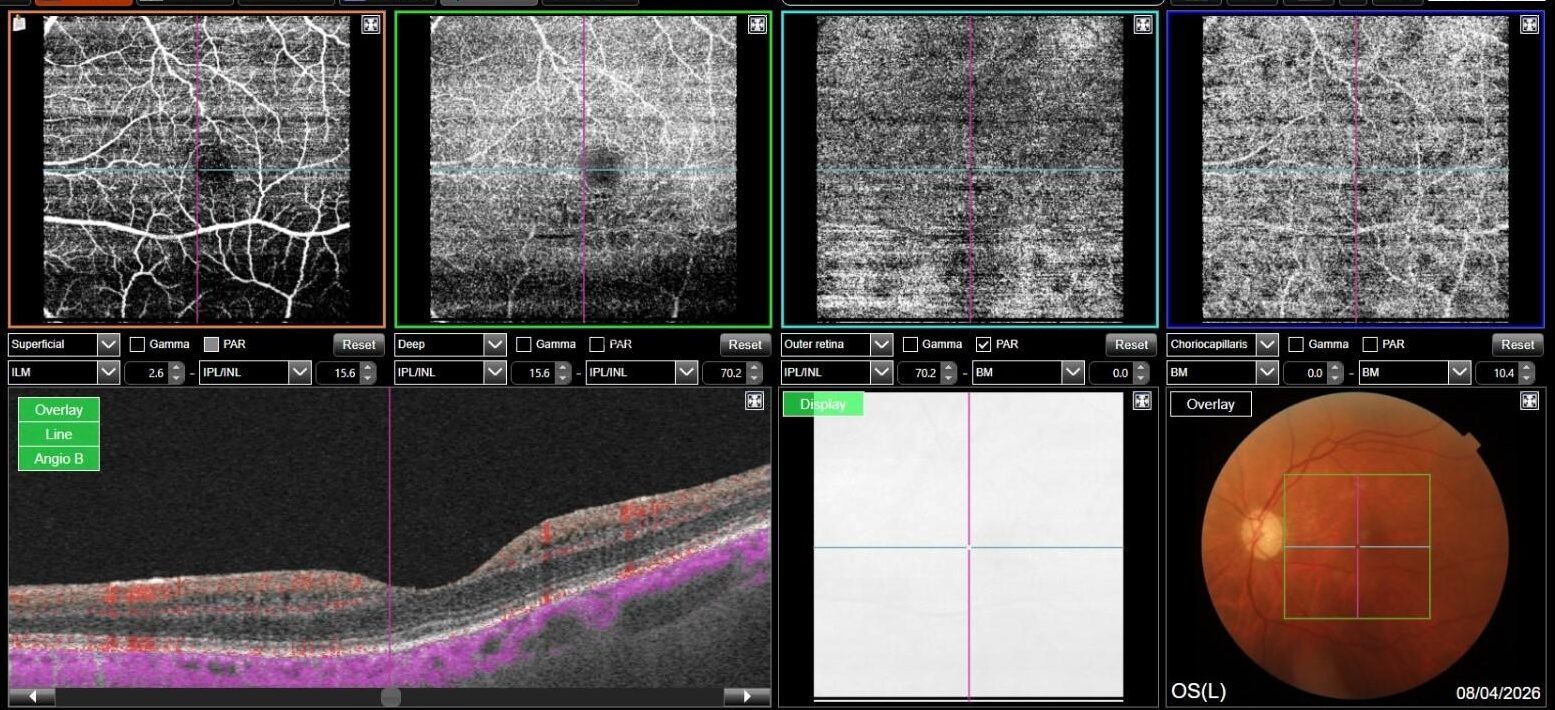

OCT-A was also performed in OS and, as expected, turned out to be negative. This also allowed an OCT en-face acquisition and subsequent segmentation at INL, which clearly showed the perifoveal distribution pattern of the INL cystic spaces previously found on b-scan OCT, with complete encompassing of the fovea and relative predominance in the inferior macular region.

That being said, our case allows for some interesting considerations: on one hand, MME was only found in her left eye, where the optic neuropathy was more severe, thus confirming the available literature data; on the other hand, however, en-face OCT clearly shows involvement of both inferior and superior hemiretina, although a relatively prevalent involvement of inferior hemiretina can be observed. This could either be explained by a more diffuse and severe RNFL and GC involvement, as demonstrated by both RNFL and GCC analysis, or by cohexistance of other, previously unrecognized optic neuropathy in addition to glaucomatous optic neuropathy. Lastly, no ERM was found on OCT, thus complying with evidence suggesting that vitreomacular traction may play a role in MME formation, but mainly as a concurrent cause rather than a primary pathogenetic element.